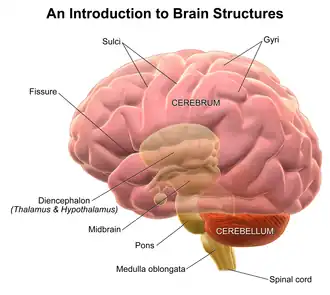

The gustatory nucleus is the rostral part of the solitary nucleus located in the medulla oblongata. The gustatory nucleus is associated with the sense of taste[1] and has two sections, the rostral and lateral regions.[2] A close association between the gustatory nucleus and visceral information exists for this function in the gustatory system, assisting in homeostasis - via the identification of food that might be possibly poisonous or harmful for the body.[3] There are many gustatory nuclei in the brain stem. Each of these nuclei corresponds to three cranial nerves, the facial nerve (VII), the glossopharyngeal nerve (IX), and the vagus nerve (X) [3] and GABA is the primary inhibitory neurotransmitter involved in its functionality.[4] All visceral afferents in the vagus and glossopharyngeal nerves first arrive in the nucleus of the solitary tract and information from the gustatory system can then be relayed to the thalamus and cortex.[5]

The central axons on primary sensory neurons in the taste system in the cranial nerve ganglia connect to lateral and rostral regions of the nucleus of the solitary tract which is located in the medulla and is also known as the gustatory nucleus.[3] The most pronounced gustatory nucleus is the rostral cap of the nucleus solitarius which is located at the ponto-medullary junction. Afferent taste fibers from the facial and from the facial and glossopharyngeal nerves are sent to the nucleus solitarius. The gustatory system then sends information to the thalamus which ultimately sends information to the cerebral cortex.

Furthermore, the gustatory nucleus is connected via the pons to the thalamocortical system consisting of the hypothalamus and the amygdala.[6] These connections can stimulate appetite, satisfaction, and other homeostatic responses that have to do with eating.[3] Distributed throughout the dorsal epithelium of the tongue, soft palate, pharynx, and upper part of the esophagus are taste buds that contain taste cells, which are peripheral receptors involved in gustatory system and react to chemical stimuli.[3] Different sections of the tongue are innervated with the three cranial nerves. The facial nerve (VII) innervates the anterior two-thirds of the tongue, the glossopharyngeal nerve (IX) innervates the posterior one-third and the vagus nerve (X) innervates the epiglottis.[8]

The study of the nucleus usually involves model organisms like fish, hamsters, and mice.[7][9][10] Studies with humans involve MRIs and PET scan.[2][11] A study done on monkeys found that when a given food is consumed to the point that a monkey is full and satisfied, specific orbitofrontal neurons in the monkey direct their firing towards that stimulus which indicates that these neurons are used in motivating one to eat as well as not to eat. In addition, the gustatory system has been greatly studied in some cyprinoid and cobitoid fish species because of their enormously hypertrophied peripheral gustatory nerves. The major difference between the gustatory neural structure of the fish and the rat is that the secondary gustatory nucleus of the fish projects to the interior lobe's lateral lobule of the diencephalon, while in the rat, the secondary gustatory nucleus projects to a specific thalamic area in the ventrobasal complex and to the ventral forebrain and rostroventral diencephalon.[5]